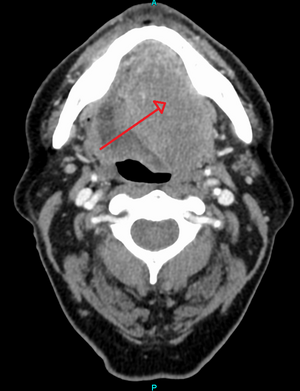

سرطان الخلايا الحرشفية كبير الحجم في اللسان كما يظهر في صورة بالأشعة المقطعية.

حوالي 90%[4] من حالات سرطان الرأس والعنق (سرطان الفم، تجويف الأنف، البلعوم الأنفي، الحلق، والهياكل المرتبطة به) ترجع إلى سرطان الخلايا الحرشفية.